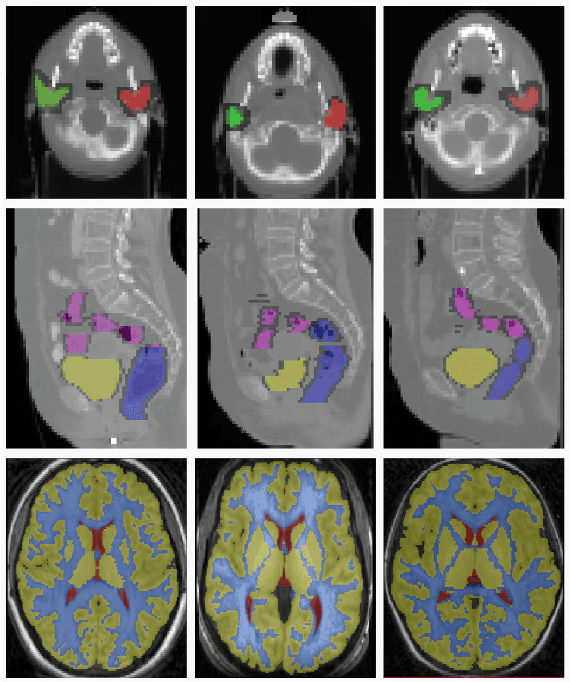

Abstract:Deformable registration has been one of the pillars of biomedical image computing. Conventional approaches refer to the definition of a similarity criterion that, once endowed with a deformation model and a smoothness constraint, determines the optimal transformation to align two given images. The definition of this metric function is among the most critical aspects of the registration process. We argue that incorporating semantic information (in the form of anatomical segmentation maps) into the registration process will further improve the accuracy of the results. In this paper, we propose a novel weakly supervised approach to learn domain specific aggregations of conventional metrics using anatomical segmentations. This combination is learned using latent structured support vector machines (LSSVM). The learned matching criterion is integrated within a metric free optimization framework based on graphical models, resulting in a multi-metric algorithm endowed with a spatially varying similarity metric function conditioned on the anatomical structures. We provide extensive evaluation on three different datasets of CT and MRI images, showing that learned multi-metric registration outperforms single-metric approaches based on conventional similarity measures.